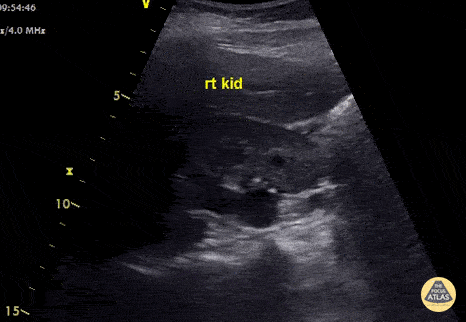

Renal/GU - Hydroureter with Moderate Hydronephrosis

This young lady presented with clinical features of pyelonephritis - fever, rigors and right flank pain. Renal US shows moderate hydronephrosis and hydroureter. CT showed a 5.7mm right mid ureteric stone. Nephrostomy tube was placed to decompress obstructive uropathy. Ultrasound is insensitive for pyelonephritis - most patients have normal scans. POCUS can be used to check for hydronephrosis, renal abscess, pyonephrosis or emphysematous pyelonephritis as these findings will alter management. Images recorded by Dr. Khaled Taha Submitted by Dr Cian McDermott Mater University Hospital, Dublin, Ireland